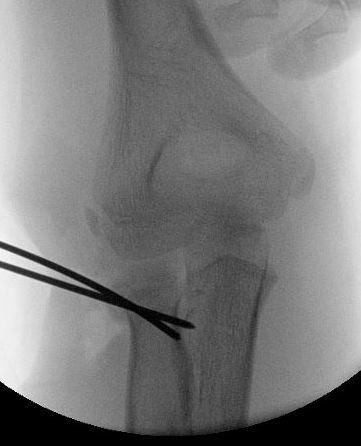

Radial neck fracture and olecranon fracture

Percutaneous K wire

Technique

Pronate arm to protect PIN

- insert into fracture site

- lever fracture into reduced position

- then drive into opposite cortex